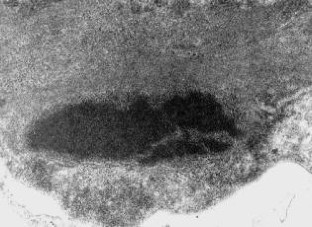

Die Lupusnephritis ist ein bekanntes Phänomen beim systemischen Lupus erythematodes (SLE). Wir untersuchten die Nierenbiopsie einer 30-jährigen Frau mit SLE. Die Anamnese zeigte einen klinisch typischen SLE mit generalisierten Symptomen mit positivem ANA- und Anti-ds-DNA-Titer ohne Nachweis von Lupuskoagulans, des Rheumafaktors, von Kryoglobulinen sowie ohne Antiphospholipid-Antikörper. Eine Paraproteinämie war weder für IgG noch für IgA oder IgM nachzuweisen. Mit Hilfe der Lichtmikroskopie, der Elektronenmikroskopie sowie der Immunelektronenmikroskopie wurden elektronendichte Ablagerungen in subepithelialer, subendothelialer und mesangialer Lokalisation nachgewiesen. Zusätzlich fanden wir sowohl in den elektronendichten Ablagerungen, als auch im angrenzenden Mesangium Kristalle eines elektronendichten Materials. Diese kristallinen Strukturen sind aus IgG und κ-Leichtketten zusammengesetzt, während IgM, IgA sowie λ-Leichtketten mittels Immunelektronenmikroskopie nicht nachzuweisen waren.

Lupus nephritis is a common phenomenon in Systemic Lupus Erythematosus (SLE). We analyzed a renal biopsy of a 30-year-old woman with SLE. The clinical history showed a typical SLE with generalized symptoms without demonstrable lupus coagulant, positive for anti-nuclear antibodies and anti-ds-DNA antibodies but negative for rheumatoid factor, cryoglobulins and antiphospholipid antibodies. A paraproteinemia for IgA, IgG and IgM was not detectable. Using light, electron and immunoelectron microscopy electron-dense deposits were noted in subepithelial, subendothelial and mesangial position. Most remarkably, the electron-dense deposits and mesangial areas in the vicinity of deposits contained an electron-dense crystalline material. The crystalline structures were composed of IgG and kappa light chains, while they were negative for IgM, IgA and lambda light chains, as demonstrated by immunoelectron microscopy.

As far as we know, this is the first case of lupus nephritis with crystalline structures. Since we could not detect cryoglobulinemia or paraproteinemia, other mechanisms possibly favor organization of macromolecular structures.